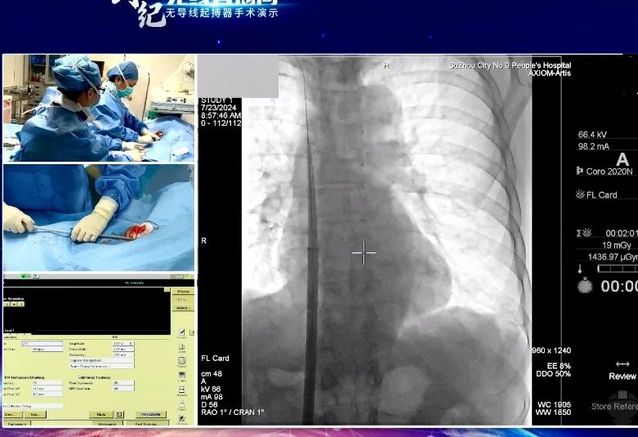

7月24日,“创势纪·无线直播间—苏皖区域无导线起搏器手术演示”在线上举行,苏州九院心血管内科主任吴雁鸣参与手术演示,助力提升区域心血管病防治水平。本次活动由江苏省医学会心血管病学分会副主任委员、苏州市心血管病学分会主任委员、苏州大学附属第一医院心内科主任蒋廷波主持,汇聚了一大批专家教授开展手术演示和线上探讨,通过学术交流积极推动苏皖地区心血管病防治水平的进一步提高。

早在2021年,苏州九院心血管内科就积极引入和开展无导线心脏起搏器植入术,是我区首家成功独立开展无导线起搏器植入手术的医院。心血管内科主任吴雁鸣是我区首位独立无导线起搏器术者,目前已成功独立植入近30例,受益人群大多为高龄老人,其中年龄最大的患者接受手术时已经103岁。

无导线起搏器,代表心脏起搏领域**技术。无导线起搏器(Micra),俗称胶囊起搏器,是目前世界上最小最轻的起搏器,直径6.7mm,长度25.9mm,重量仅1.75g,是国际前沿的先进起搏技术。虽然小,但其电池续航能力强,工作寿命长达12年,植入后还可以接受1.5T/3.0T核磁共振检查。患者无切口、无伤疤、无凸起、无束缚,几乎感觉不到它的存在,是看不见的起搏器,就像默默守护心律失常患者心脏健康的“隐性保镖”。

这一技术的成熟推广,对区域患者健康有着重要意义。植入心脏起搏器主要针对严重缓慢性心律失常的患者。传统的心脏永久起搏器由脉冲发生器和电极导线组成,医生通过腋静脉或锁骨下静脉将起搏器电极导线送至右心房或右心室,在患者胸前区胸大肌处制作与起搏器大小合适的囊袋,以容纳脉冲发生器。无导线起搏器不同于传统起搏器的地方在于:它不需要使用导线将脉冲发生器连接到起搏电极上。相反,它将脉冲发生器和起搏电极集成在一起,以微缩胶囊的形式直接植入患者的心腔内部。